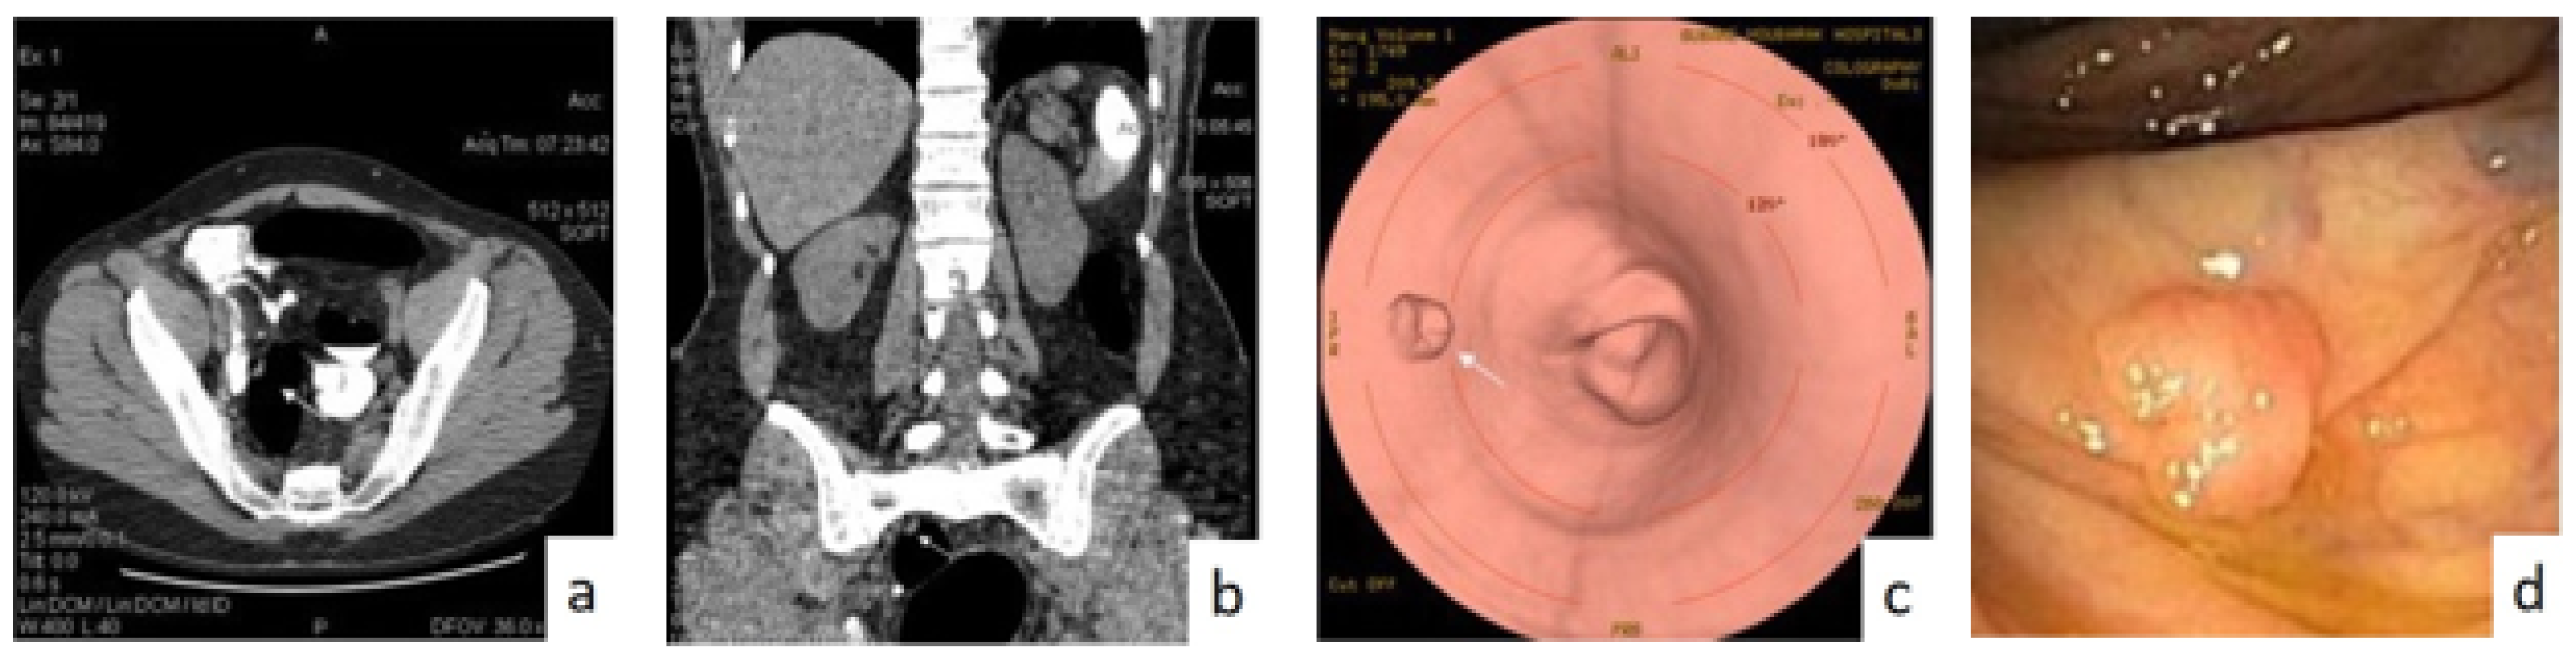

3.1.1. Virtual Computed Tomography Colonoscopy (CTC)

3.1.2. Magnetic Resonance Imaging (MRI) and Endorectal Ultrasound (ERUS)